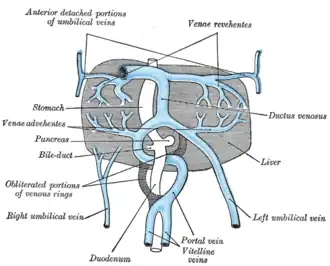

The liver and the veins in connection with it, of a human embryo, twenty-four or twenty-five days old, as seen from the ventral surface. | |